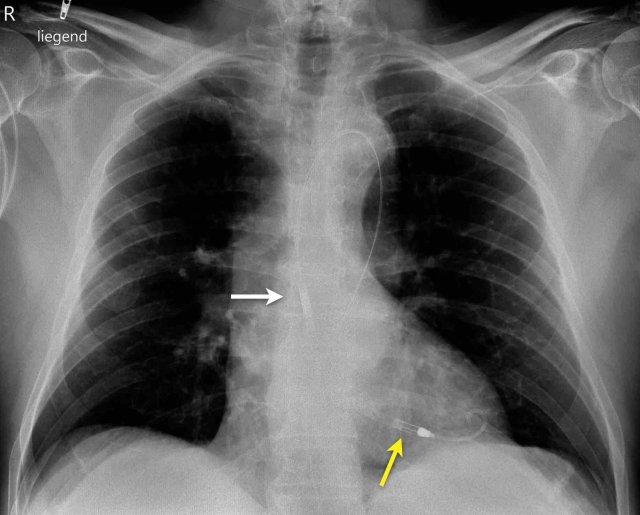

Bệnh nhân này đã được sửa chữa ba van:

- Van hai lá

- Van ba lá

- Van động mạch chủ

Có máy tạo nhịp tim với điện cực thượng tâm mạc.

Phương án này được lựa chọn vì người ta cho rằng điện cực đặt theo đường thông thường vào thất phải sẽ ảnh hưởng quá nhiều đến chức năng của van ba lá nhân tạo.

Mũi tên trắng chỉ vào van động mạch chủ.

Mũi tên vàng chỉ vào van hai lá.